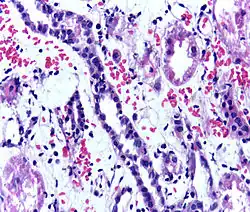

Presence of lymphocytes within the tubular epithelium, attesting to acute cellular rejection of a renal graft. Biopsy sample.

Acute rejection is another possible complication of kidney transplantation; it is graded according to the Banff Classification, which incorporates various serologic, molecular, and histologic markers to determine the severity of the rejection. Acute rejection can be classified as T-cell-mediated, antibody-mediated, or both (mixed rejection). Common causes of acute rejection include inadequate immunosuppression treatment or non-adherence with the immunosuppressive regimen.[79] Clinical acute rejection (seen in approximately 10-15% of kidney transplants within the first year of transplantation) presents as kidney rejection with associated kidney dysfunction.[79] Subclinical rejection (seen in approximately 5-15% of kidney transplants within the first year of transplantation) presents as rejection incidentally seen on biopsy but with normal kidney function.[79] Acute rejection with onset 3 months or later after transplantation is associated with a worse prognosis.[79] Acute rejection with onset less than 1 year after transplantation is usually T cell mediated, whereas onset greater than 1 year after transplantation is associated with a mixed T cell and antibody-mediated inflammation.[79]